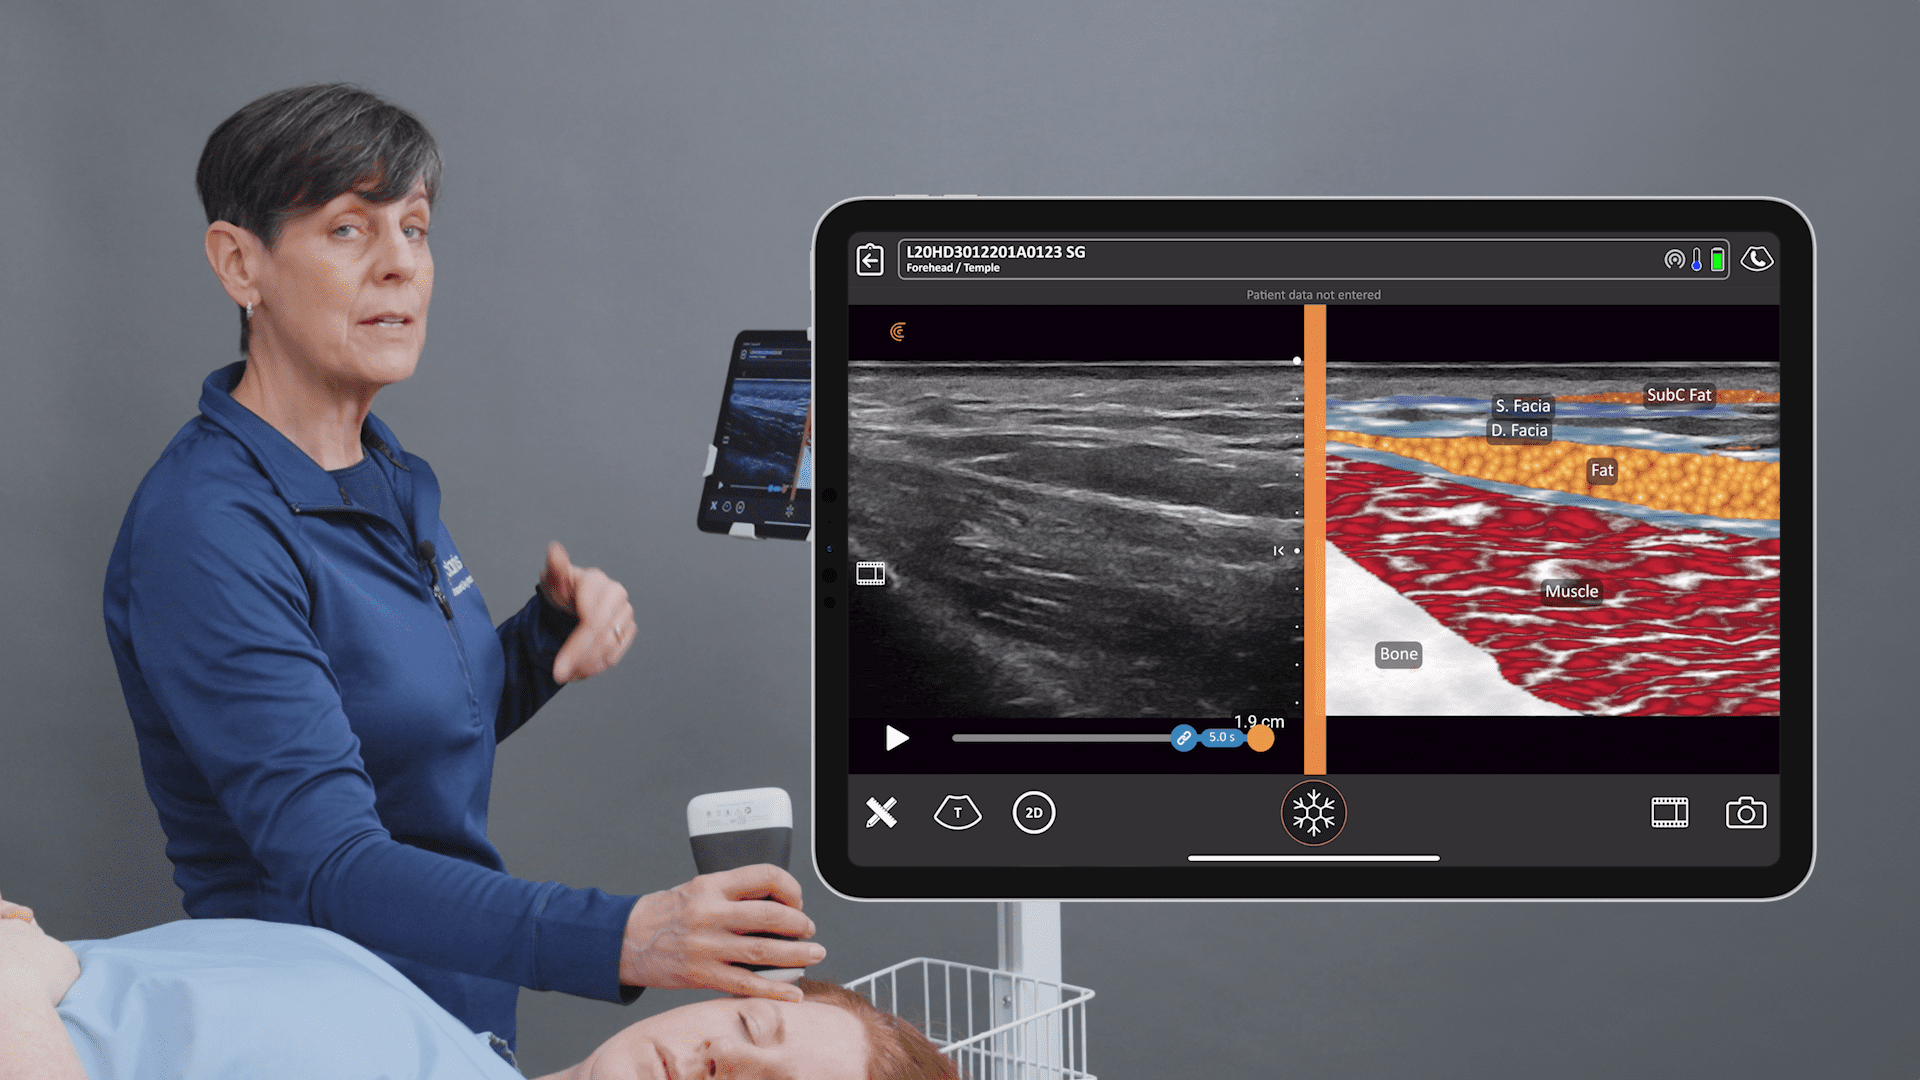

Setting Up for the Exam

This is my setup in a regular exam room. I’m using the new Clarius L7 HD device with an iPad. I bought a bracket online for under $100 and hooked it to the back of the chair so that I can touch the screen if I need to. But I usually use the buttons on the device instead of touching the screen. I’ve programmed the bottom button to freeze the image and the top button to save the image. To record a video, I push the bottom button and a little icon appears that looks like a movie camera – it will take a 10-second video and stores it on the iPad and then upload it to the Cloud at the end of the exam. It’s very simple to do from the room.

Recognizing a Normal Textured Breast Implant

When looking for pathology, we have to know what normal looks like. This is a Sientra textured implant. You can see the breast parenchyma up above where it says breast, so it’s skin, a little bit of subcutaneous fat and then the dense white breast parenchymal tissue with those little striations, which are the support structures. And then the white line that’s just underneath the parenchyma, or under the muscle if it’s a submuscular implant, is the capsule. Usually, the implant shell is a bilaminar structure. And when you look in really high definition, sometimes it will look like it has three different lines, with the fourth line being the capsule that’s just above. That’s a normal, unbroken implant.